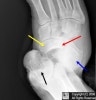

X-ray : Chopart injury